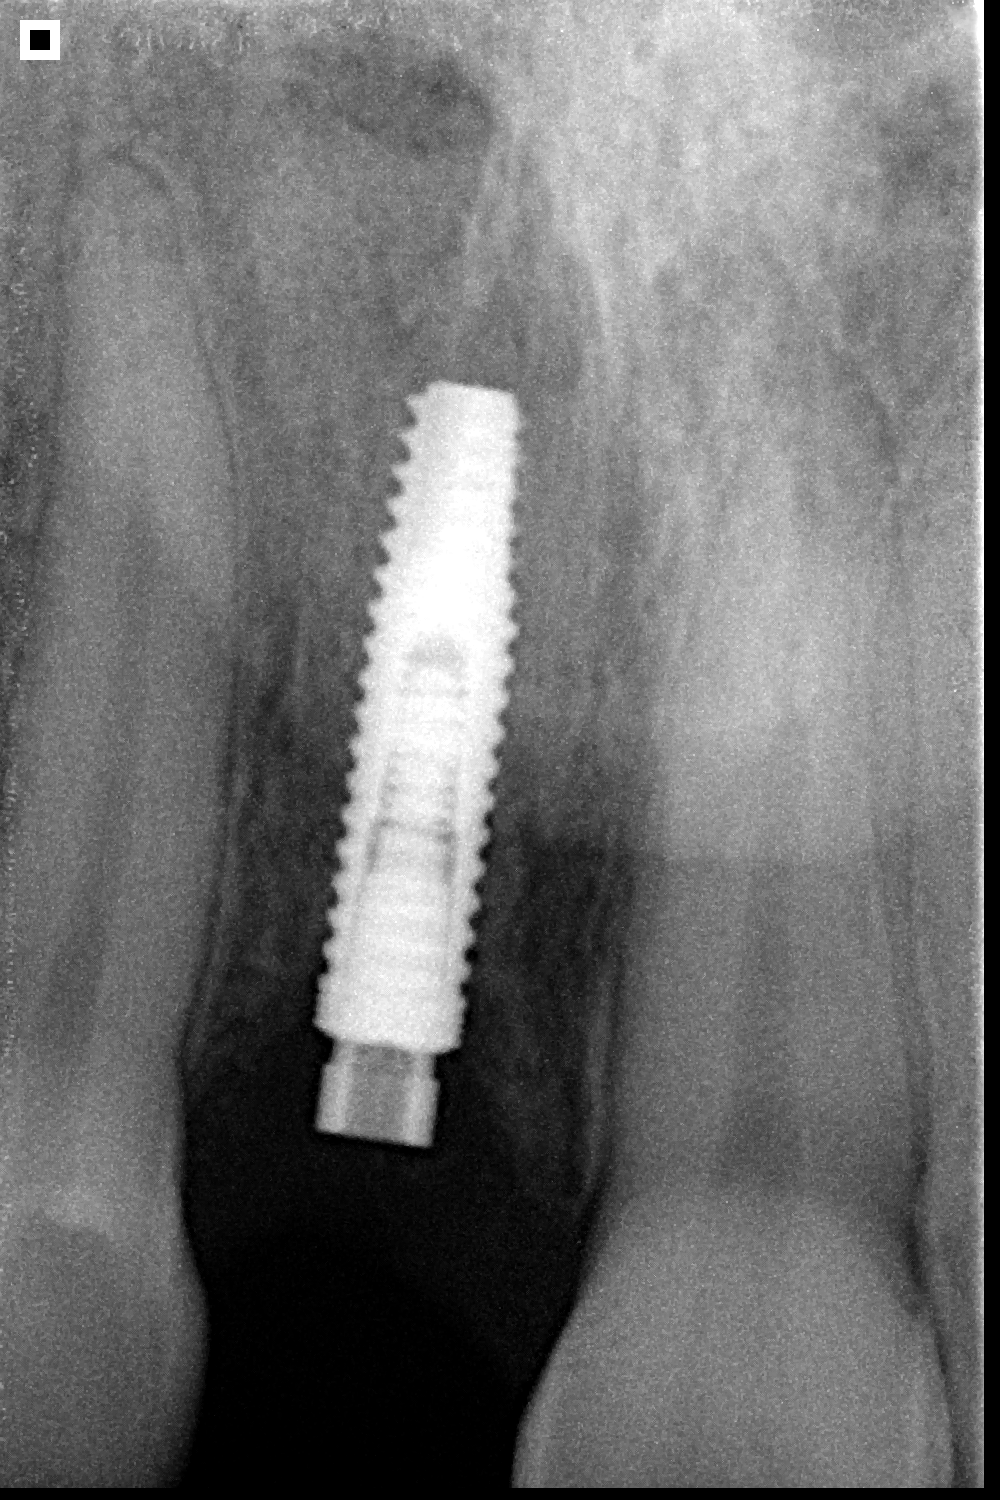

UNITITE PRIME

Indicado para carga inmediata, precoz o tardía: Unitite ha sido diseñado para situaciones desafiantes.

Cicatrización de alta calidad: La cicatrización híbrida de Unitite elimina la fase catabólica de remodelación ósea interfacial en la mayor área del implante, lo que acelera el proceso de cicatrización y mejora la calidad del tejido óseo formado.

Alta hidrofilia: Con una capa de aproximadamente 20nm de hidroxiapatita, el Unitite amplía la actividad de las proteínas que participan en el proceso de osteointegración.

La macrogeometría exclusiva asegura la precisión entre el sistema de fresado y el diseño de las roscas externas, combinando alta estabilidad y disminuyendo la compresión del tejido óseo de cicatrización periimplantaria.

Con microespiras de 0.2 a 0.5 mm, Unitite interacciona con el tejido óseo y alta resistencia mecánica.